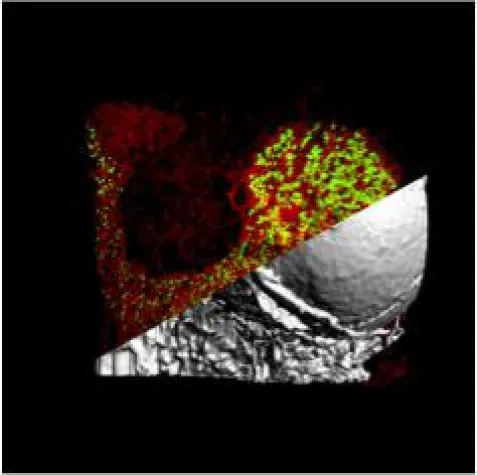

Bisher dachte man, dass sich die Vorläuferzellen mühsam ihren Weg durch das Knochenmark bis zum Gefäß bahnen müssen. Mit modernen Mikroskopieverfahren und computerbasierten Simulationen konnten Forscher des Rudolf-Virchow-Zentrums für Experimentelle Biomedizin und des Universitätsklinikums Würzburg diese Theorie jetzt widerlegen. Wie sie zeigen konnten, entstehen die meisten Megakaryozyten bereits in der vaskulären Nische, also unmittelbar am Gefäß. Die übrigen Vorläuferzellen sind gleichmäßig im Knochenmark verteilt und typischerweise so groß und formflexibel, dass sie durch kleinste (Wackel-) Bewegungen im dichten Gefäßnetz des Knochenmarks das Gefäß erreichen können.

„Erst die Kombination aller Informationen aus Intravital- und Lichtblattblattmikroskopie hat diese Erkenntnisse möglich gemacht“, sagt Prof. Katrin Heinze, Leiterin der Studie. Weiter erklärt sie: „Wir konnten zudem zeigen, wie die 3D-Bilder der Gefäße und Zellen zu perfekten biologischen Vorlagen für computergestützte, realistische Simulationen der Zellverteilung im Knochenmark werden können“.

Dr. David Stegner, Erstautor der Studie, ergänzt: „Wir haben schon länger vermutet, dass die existierenden Modelle der Thrombopoese unzureichend oder falsch sind, es war jedoch schwierig, das experimentell zu beweisen." Mit ihrem neuen Ansatz ist es dem Forscherteam jetzt erstmals gelungen, hochauflösende Einblicke in den intakten Knochen zu bekommen. Die beiden Federführenden der Studie weisen darauf hin, dass ihre Kollaboration nicht nur ein Glücksfall, sondern auch eine zukunftsweisende Entscheidung gewesen sei, die noch lange tragen werde.